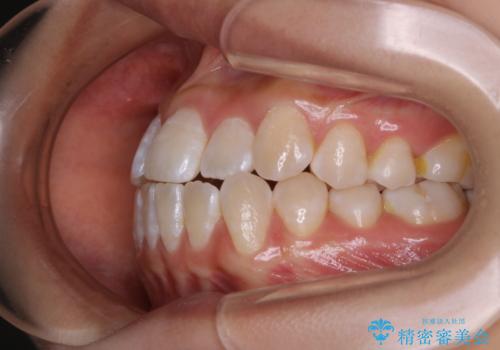

前歯のがたつきとオープンバイト:インビザラインでまとめて治す

- 噛み合わせと、前歯のがたつきが気になるとご相談にいらした方です。インビザラインFULLで綺麗な歯並びと噛み合わせを作ることが出来ました。

オープンバイトの方への治療は、通常抜歯を行いワイヤーによる矯正治療を行うことが多いですが、今回はインビザラインの特性を生かし、非抜歯にて綺麗な歯並びを作ることが出来ました。